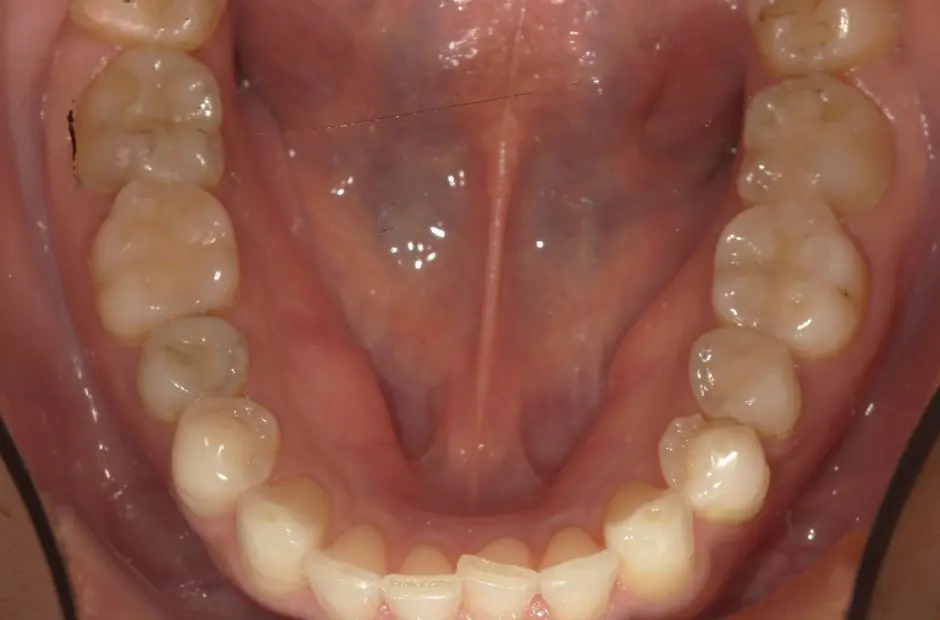

case.02

金属アレルギー治療の症例・治療前写真(銀歯7本)

金属アレルギー治療の症例・治療後写真(銀歯7本)

「 メタルフリーで、健康を手に! 」

当サロンのメタルフリー治療は、金属アレルギーの心配を排除し、健康な口内環境を実現します。高品質な非金属素材で安心と健康を手に入れましょう。

治療内容 古い銀歯を取り除き、レジンとセラミックを組み合わせて装着

治療期間/回数 2ヶ月/通院6回

費用 220,000円(税込)(検査・診断、手術関連処置費用、レジン装着の費用等は含まない)e-maxインレー:55,000円/1カ所

リスク/副作用 咬合による割れ